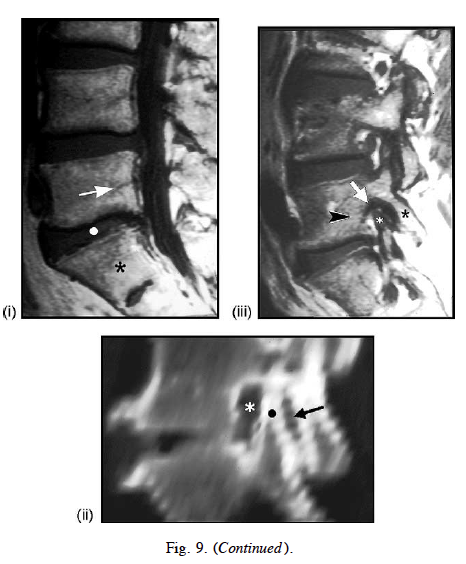

Fig. 9. Degenerative retrolisthesis associated with intervertebral disk collapse and degeneration of related spinal structures.

(A) Degenerative retrolisthesis with central spinal canal stenosis. With intervertebral disk collapse and degeneration of related spinal structures (e.g., intraspinal ligaments, degenerative retrolisthesis may occur (dashed arrows). This results in stenosis of the central spinal canal (double-headed arrow).

(B) Anteroposterior posterior spinal facet (i.e., zygapophyseal) joint dislocation. With the retrolisthesis of the suprajacent vertebral body (dashed arrow), there will be an anteroposterior posterior spinal facet joint dislocation (asterisk) associated with a joint effusion (coarse stippling). This will narrow the anteroposterior diameter of the spinal neural foramen (solid arrow). In addition, the apex of the superior articular facet process (dot) may protrude directly into the superior recess of the spinal neural foramen.

(C) Erosion of the apex of the superior articular facet process and pedicle. With further disk collapse there maybe an excavative erosion

of the apex of the superior articular facet process and suprajacent pedicle (shading).

(D) Medical imaging studies: (i) midline sagittal T1-weighted MRI showing partial disk collapse at L5-S1 (dot) associated with very

minor degenerative retrolisthesis of L5 (arrow) on S1 (asterisk; compare with (A)). (ii) Parasagittal CT reconstruction showing anteroposterior posterior spinal facet joint space “gapping” (arrow) resulting from relative anterior displacement of the superior facet process of S1 (dot) into the spinal neural foramen causing anteroposterior narrowing of the foramen (asterisk; compare with (B)). (iii) Parasagittal T1-weighted MRI showing minor retrolisthesis of L5 (arrowhead) on S1, with anterior displacement of the superior articular facet process (white asterisk) of S1 into the superior recess of the spinal neural foramen resulting in foraminal stenosis (arrow); there is relative consonant posterior displacement of the inferior articular process of L5 (black asterisk) compare with (B)).